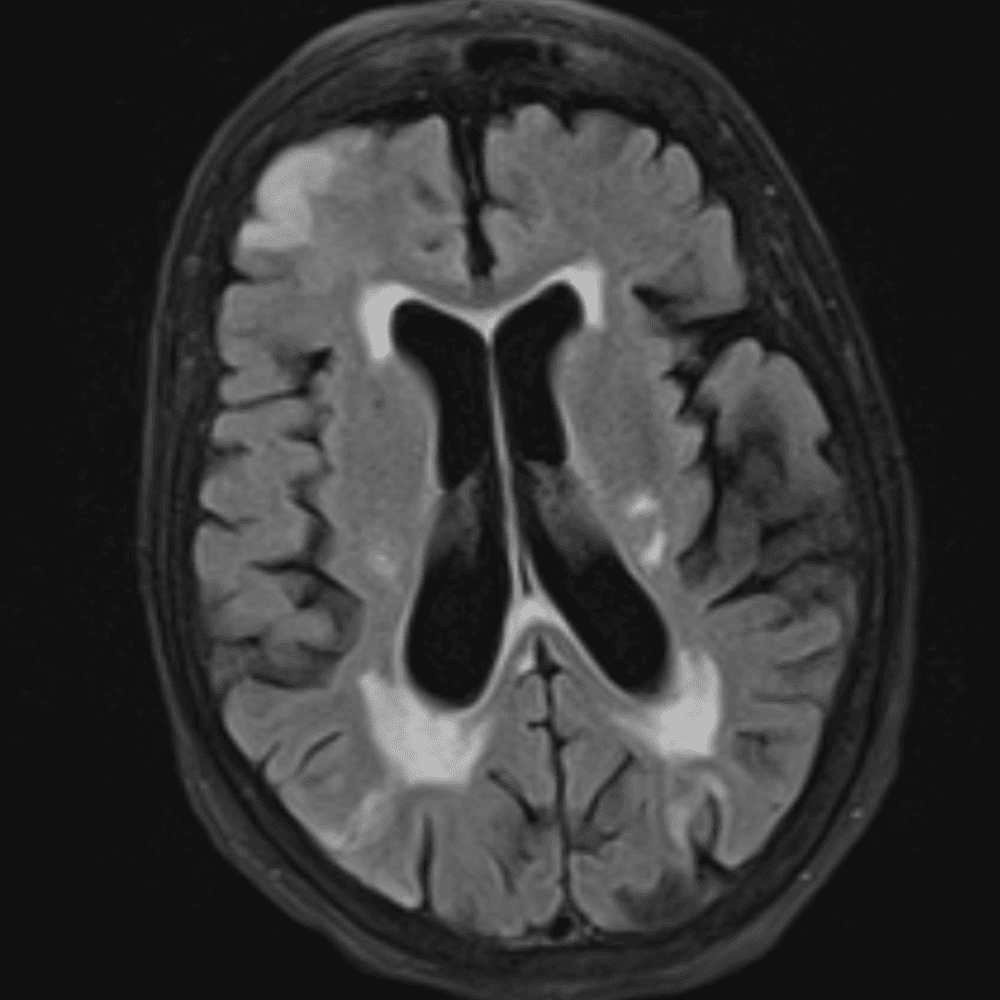

๋‹น์ง ์‹œ ํ”ํžˆ ๋ณผ ์ˆ˜ ์žˆ๋Š” ์‚ฌ๋ก€์˜ ์ „ํ˜•์ ์ธ ์˜ˆ๋ฅผ ํฌํ•จํ•ฉ๋‹ˆ๋‹ค.

39 ์‚ฌ๋ก€

์—ฐ์Šต

๋ฏธ๋ฌ˜ํ•˜๊ฑฐ๋‚˜ ์–ด๋ ค์šด ์‚ฌ๋ก€์™€ ์ผ๋ถ€ ์ •์ƒ ์‚ฌ๋ก€๋ฅผ ํฌํ•จํ•˜์—ฌ ๋‹น์ง์„ ์‹œ๋ฎฌ๋ ˆ์ด์…˜ํ•ฉ๋‹ˆ๋‹ค.

50 ์‚ฌ๋ก€